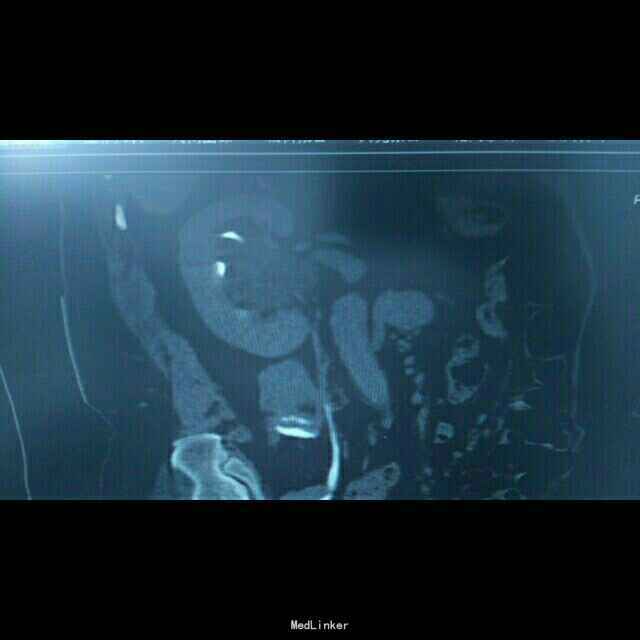

68岁,女性。 主诉:左侧腰痛1年,加重1个月。 病史:1年前无明显诱因出现左侧腰痛,无恶心呕吐,无肉眼血尿。1个月前加重,于外院查泌尿系彩超显示:左肾积液,输尿管显示不清。

诊断:双肾盂旁囊肿 治疗:因患者肾盂未明显受压,疼痛症状不明显,等待观察,暂未予处理。

双侧同时出现的病例并不多见,临床只能通过泌尿系统CTU或增强CT加以鉴别,彩超无法区分肾盂积水及盂旁囊肿。